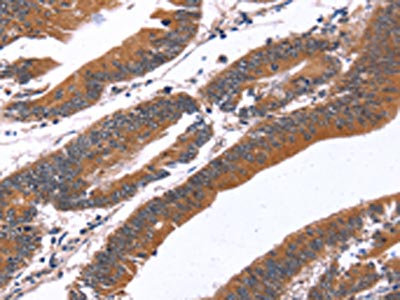

The image on the left is immunohistochemistry of paraffin-embedded Human colon cancer tissue using CSB-PA233008(GREB1 Antibody) at dilution 1/40, on the right is treated with synthetic peptide. (Original magnification: ×200)